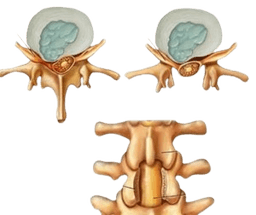

Discectomy

A discectomy is a surgical procedure to remove some part or complete part of an intervertebral disk in the spine. To explain further, intervertebral disks are like flat, round cushions that are placed between the vertebrae (bones) in the spine and work as spine shock absorbers. Each disk has a soft, gel-like centre called nucleus pulposus, surrounded by a flexible outer ring called annulus. Importantly, intervertebral disks are under regular pressure. As a result, a disk can tear, allowing some of the nucleus gel substances that come out through leaking. This condition is known as a herniated disk, also known as bulging, slipped, or ruptured disk. Consequently, this is the main reason that leads to performing a discectomy. -br In most cases, herniated disks mostly affect the lower back called the lumbar spine, but in addition, they also affect the neck called cervical spine too. However, a rare place where herniated disks are seen is the middle back. -br A discectomy in India, also spelled as diskectomy.